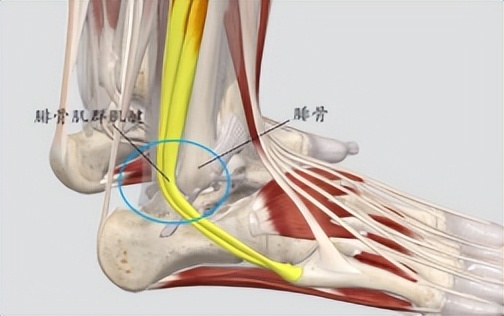

腓骨肌腱滑脱症,是指腓骨肌腱在创伤等因素作用下离开了正常的解剖位置,滑出到腓骨远端的外侧面,使腓骨肌腱失去支撑点,或者在肌腱腱鞘内改变了正常的解剖位置。

腓骨肌腱

正常情况下,腓骨上、下支持带会固定腓骨肌群的肌腱,使它在固定的位置中运动。当支持带出现松弛的时候,腓骨肌腱就特别容易滑出腓骨骨端凹槽,主要可能与以下情况有关: